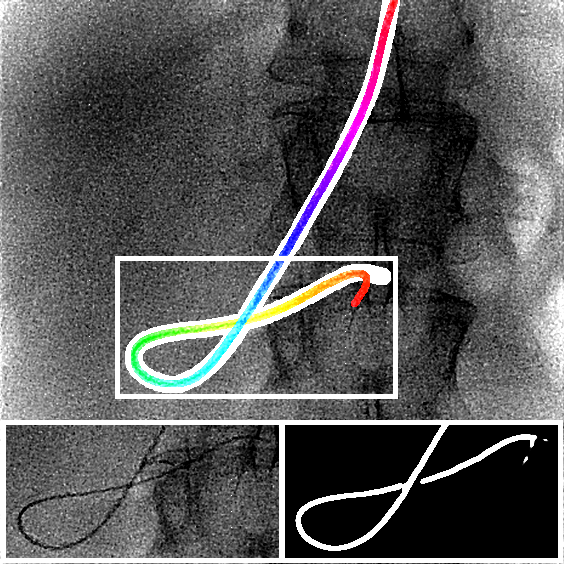

The output of the neural network is first thresholded with a threshold (between 0 and 1) and then skeletonized [19]. Next, the branches (ordered sets of pixels) are determined based on connectivity. Connection points are created between close branches. If the closest points between two branches are within a distance pixels, we consider this to be a possible connection, and there can be only one connection between two particular branches. Then, to link the branches, three steps are done (Fig. 2). First, for each connection, we divide and merge branches in order to have the longest branches. Second, loops are detected and merged following the direction at the crossing point. We have a loop in a branch when two points, within a distance pixels, have their distance along the branch of at least pixels. Before the third step, the first and second steps are repeated a second time with a distance superior to . Finally, in the last step, the remaining connected branches larger than pixels are considered as incomplete loops or straight loops due to foreshortening. We process them similarly as the second step by closing the two endpoints of their branch. When all the potential links have been processed, we keep the longest connected set of branches and choose amongst the two endpoints the farthest from the image border as the tip of the catheter centerline. Finally, the centerline is smoothed by fitting a spline.

We evaluate using the tip distance error (i.e. the distance between the annotated catheter tip and the tip of the segmented catheter), and the average distance between the manually segmented catheter and the automatically segmented catheter. Figure 3 shows the tip and catheter distances results. We compute the precision of the tip between consecutive frames. The median, average, minimum and maximum of the standard deviation per sequence of the tip distance error are respectively 0.7 mm, 4.9 mm, 0.1 mm and 55.7 mm. Five examples of segmentation are shown in Figure 4. In the third frame, the segmentation is going too far and follows part of the vertebrae. The fourth frame misses the proximal part of the catheter. The last frame is the only sequence with significant false positives. It is less noisy because it has been acquired with higher radiation dose. The neural network was not trained for such sequence.